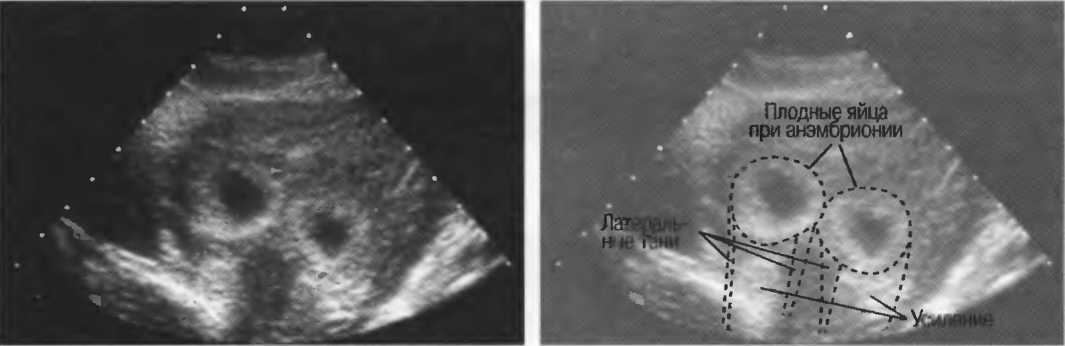

Структура, наподобие содержащей чистую жидкость кисты, визуализируется как анэхогенная зона. Стенки кисты отражают ультразвуковые сигналы под углом, и информация не поступает назад в трансдьюсер. В результате этого появляются боковые тени, но сзади кисты имеется усиление эхосигналов (усиление задней стенки) (рис. 15).

Рис. 15б. Плодные яйца при анэмбрионии: две жидкостьсодержащие структуры с задним усилением и латеральными тенями.